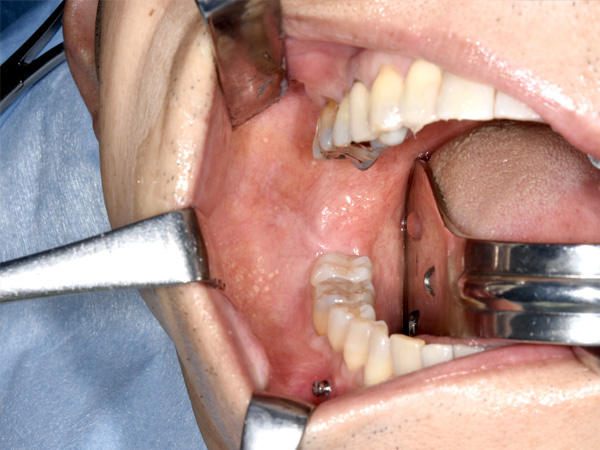

切開して、骨を露出します。

舌側の神経に気を付けながら、骨を切り始めます。

骨が切れて、分離しました。